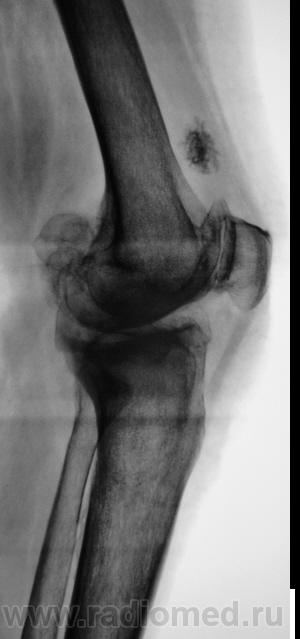

Пациентка направлена на рентгенографию коленного сустава с диагнозом "Деформирующий артроз".

Выраженный деформирующий артроз, множественные хонтроматозные тела в полости сустава.